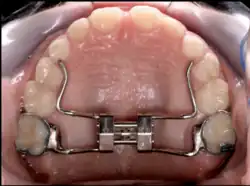

Palatal expansion

Palatal expansion can be best achieved using a fixed tissue-borne appliance. Removable appliances can push teeth outward but are less effective at maxillary sutural expansion. The effects of a removable expander may look the same as they push teeth outward, but they should not be confused with actually expanding the palate. Proper palate expansion can create more space for teeth as well as improve both oral and nasal airflow.[41]